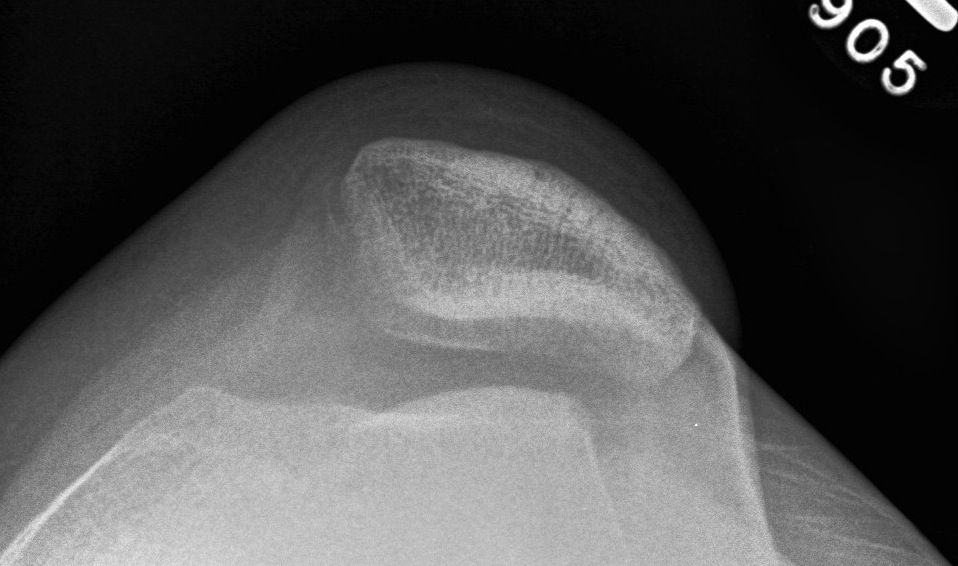

2. Assess Trochlea Dysplasia

Dejour Crossover Sign

- lateral x-ray at 30o with condyles superimposed

- identify base of trochlea

Abnormal / Crossover

- line of floor of trochlea crosses lateral lip of condyle

- indicates trochlea is deficient proximally

Trochlea depth

- < 8 mm shallow

Dejour grading system 1 - IV